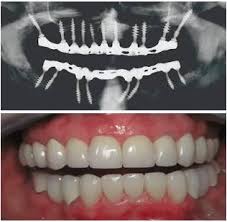

Full Mouth Dental Implants

Ideal for those who have lost all teeth in one or both arches. Multiple implants are strategically placed to support a full set of prosthetic teeth, offering improved function, stability, and appearance compared to traditional dentures.